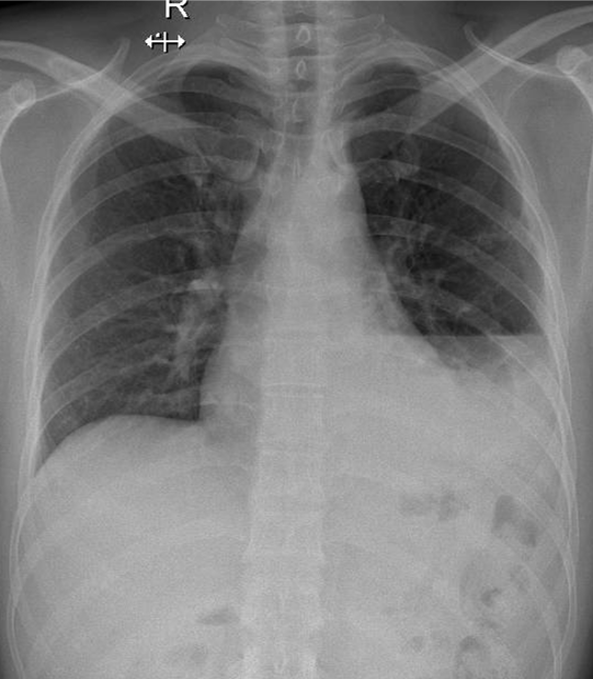

Hãy phân tích tình huống nam 38 tuổi

1-Tràn dịch + tràn khí màng phổi (T)